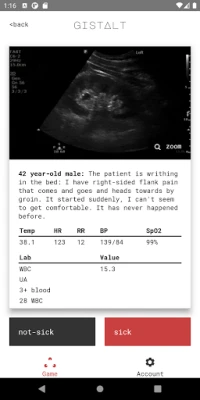

Your clinical impression (or "gestalt") about a patient's acuity is both critical and difficult to train. gistalt was designed to make it fun!

Your goal playing gistalt is to accurately identify which patients are sick (requiring hospitalization or immediate interventions for stabilization) or not-sick (conditions that can be safely treated with outpatient follow-up).

gistalt games are simple and fun. You'll start with a stack of patient presentations including vital signs, laboratory results and imaging. Swipe each card left (for not-sick) or right (for-sick) to see the next question. At the end of the stack, review your responses and see your score. Your gistalt score specially gauges your ability to detect the most critically-ill patients and institute the treatments that will make a difference.